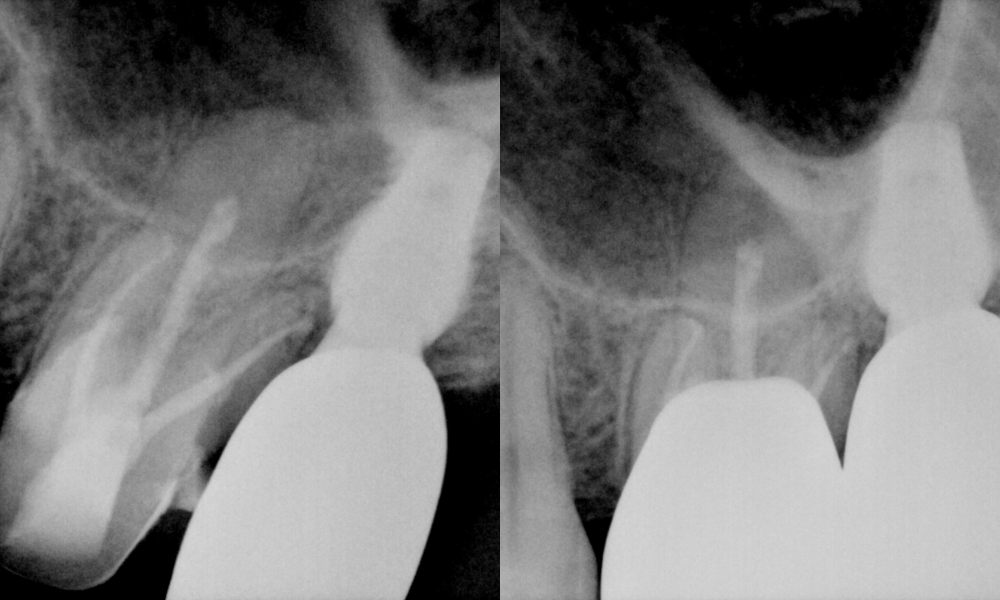

2025.05.12

X-ray 검사를 통해

파절 범위와 치아 뿌리의 상태를

면밀히 살펴본 결과

신경치료가 필요한 상태로 판단됩니다.